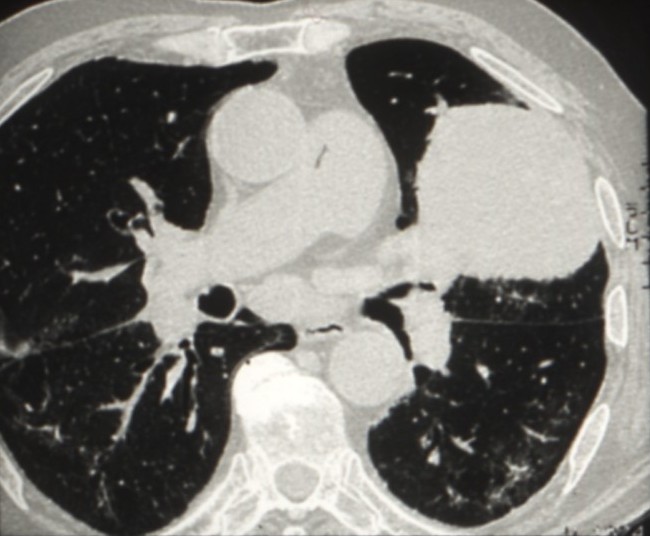

Cancers bronchiques